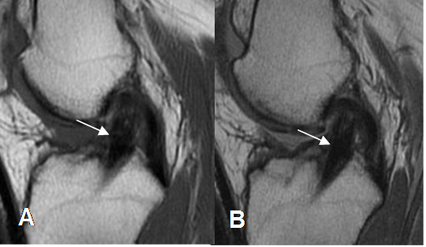

Fig 139. Ruptura parcial del injerto.

A: RM sagital en T2 y B: RM sagital en STIR. Injerto adelgazado, por ruptura parcial.

Fig 140. Ruptura del injerto.

A: RM sagital en T1. No se identifican las fibras del injerto y en su topografía existe tejido de granulación.

B: RM sagital en T2 y C: RM sagital en STIR. Ruptura casi completa del injerto, el cual está rodeado por tejido fibroso.